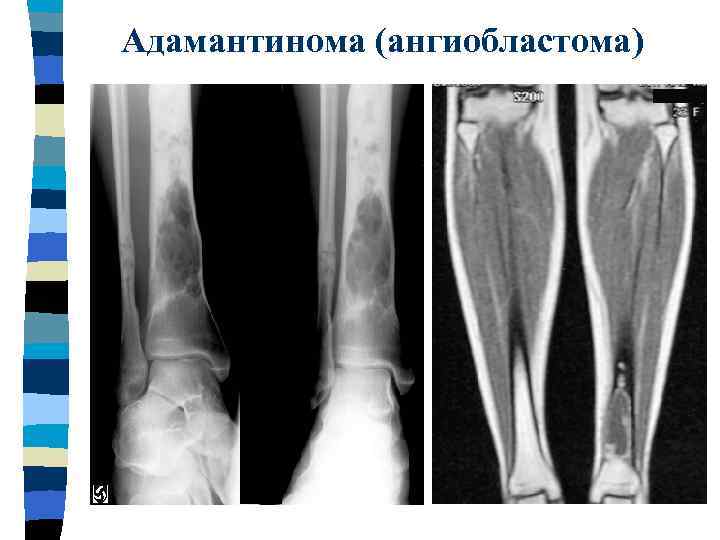

Адамантинома (ангиобластома)